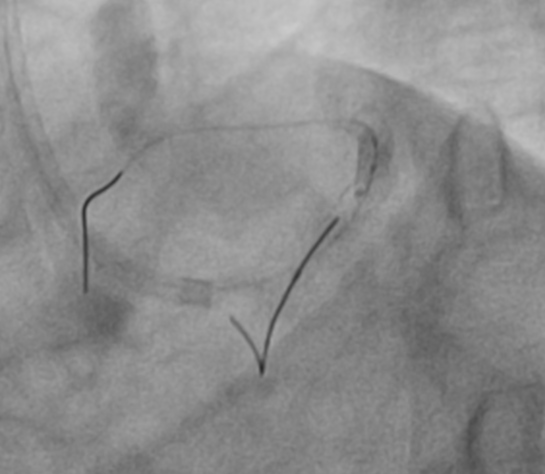

The LMCA was engaged with 7F JL 3.5 guiding catheter through right radial artery approach. The LAD lesion was crossed with one 0.014 wire and another 0.014 wire was placed in LCX. Than ostial to mid LAD lesion was sequentially predilated with 2.5x15 mm balloon, 3.0x10 mm Wolverine cutting balloon and 3.0x20 mm balloon after IVUS evaluation. After checking a 3.5x40 mm DES was positioned from LMCA to LAD. While positioning the stent patient developed VT, so immediately DC-cardioversion and chest compression was given. During this guide catheter was automatically disengaged and everything came out of coronaries. Again after careful guide catheter engagement the DES of 3.5x38 mm Ultimaster nagomi was deployed from LMCA to LAD. Than POT was done to LMCA stent with 5.0x8 mm NC balloon and LAD with 3.5x20 mm NC balloon. As LCX was dominant vessel, so kissing was done to distal LMCA with 3.5x20 mm NC balloon in LAD and 2.5x12 mm balloon in LCX.As IVUS revealed under expanded LAD stent so post dilatation done with 3.5x8 mm NC balloon at 16 atm pressure, than balloon failed to deflate. Gentle traction was applied to inflated balloon keeping negative suction ,but failed. Patient again developed VT, so DC-cardioversion was given. Trying to rupture the balloon with reverse end of BMW wire through OTW balloon, not worked. Than we used saline instead of dye with two indefaltors in three ways and negative pressure was given and that worked. Than procedure was completed with another balloon.